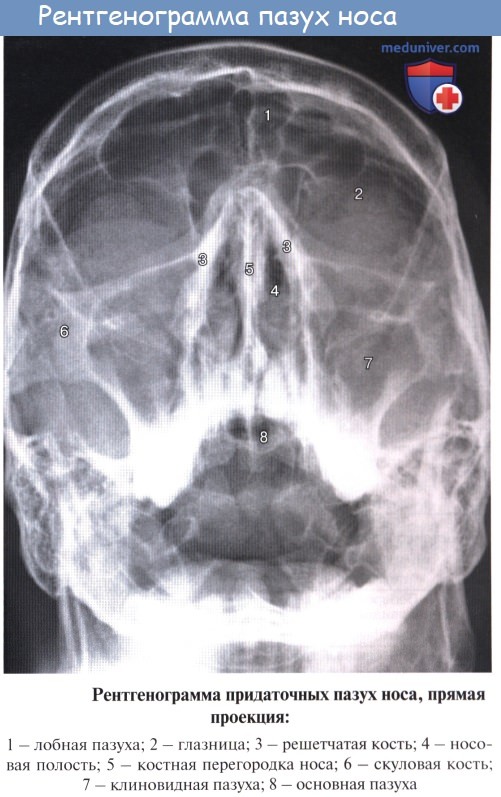

Полость носа. Слизистая полости носа. Зоны полости носа. Околоносовые пазухи.

Дополнительным приспособлением для вентиляции воздуха служат околоносовые пазухи, sinus paranasales, также выстланные слизистой оболочкой, являющейся непосредственным продолжением слизистой носа. Это описанные в «Остеологии»:

1) верхнечелюстная (гайморова) пазуха, sinus maxillaris; широкое на скелетированном черепе отверстие гайморовой пазухи закрывается слизистой оболочкой, за исключением небольшой щели;

2) лобная пазуха, sinus frontalis;

3) ячейки решетчатой кости, cellulae ethmoidales, составляющие в целом sinus ethmoidalis;

4) клиновидная пазуха, sinus sphenoidalis.